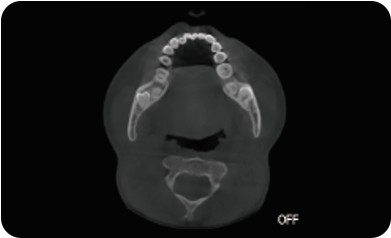

超能去伪 至臻影像

局部超清显示、 移动视野摄片

真人正侧位投影,实现CT成像区域无极可调

可根据临床需求任意调整成像区域大小实现局部超清三维显示

可根据临床需求任意调整成像区域大小实现局部超清三维显示

临床样片